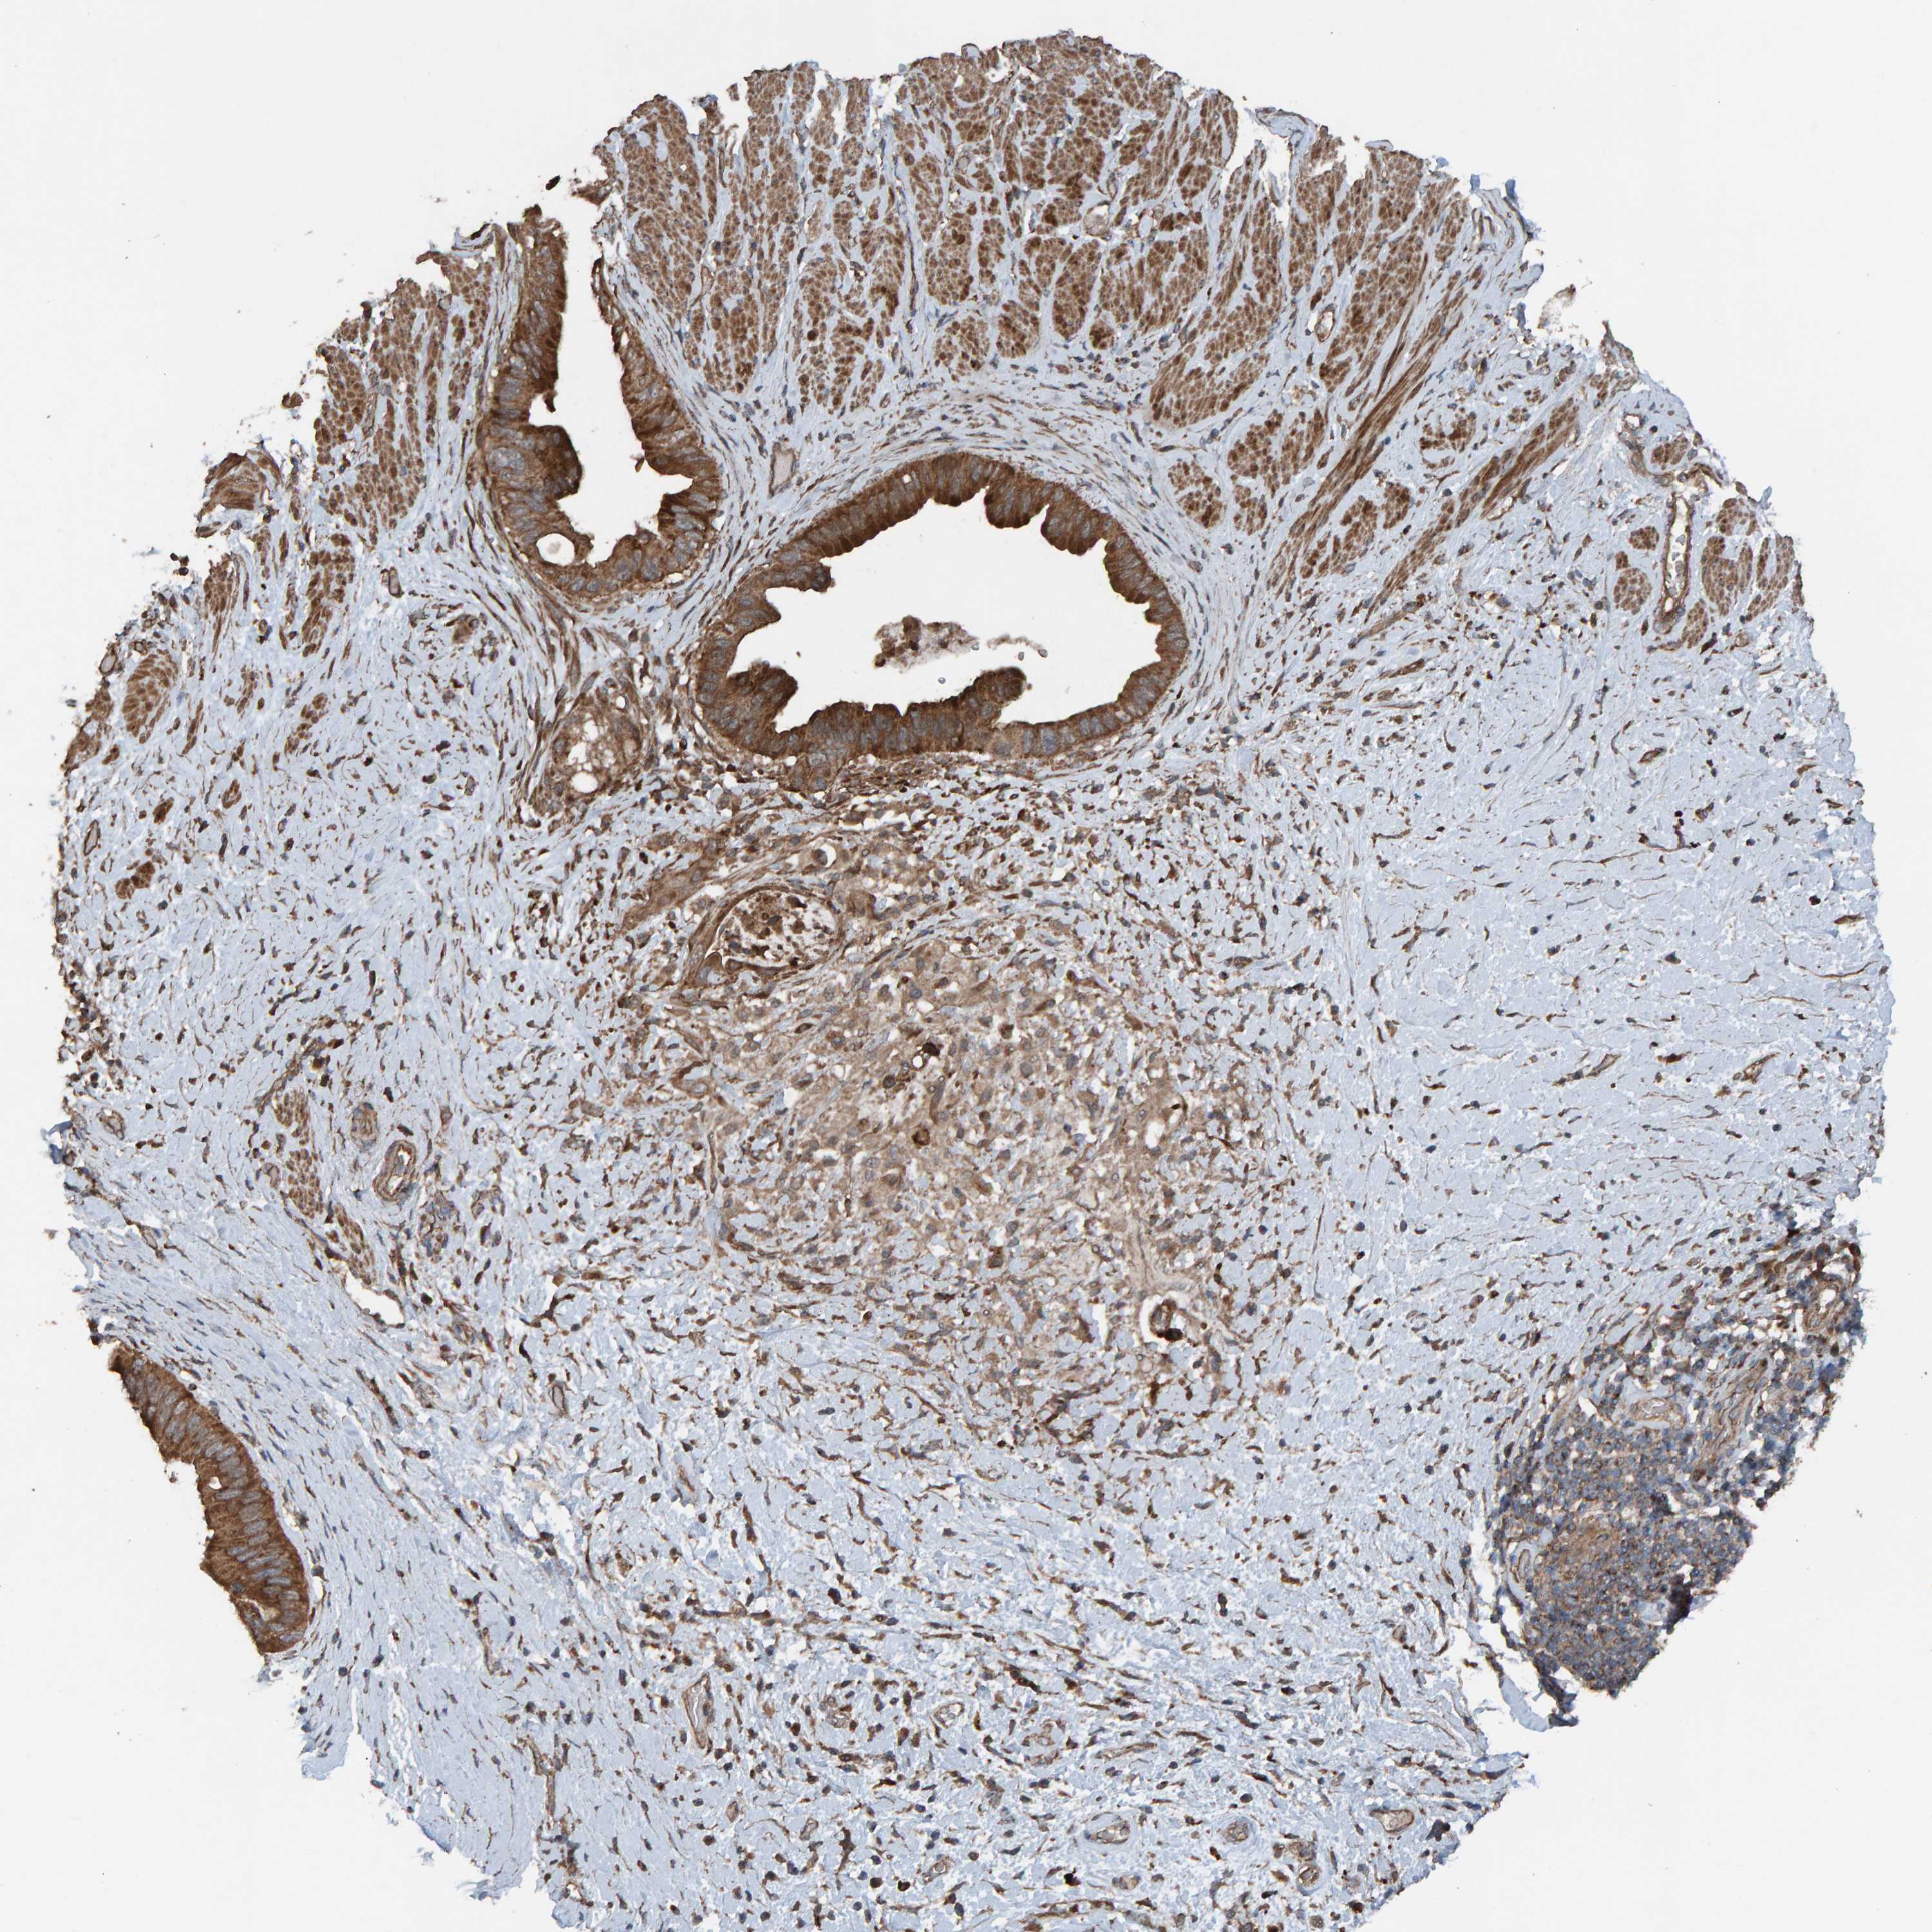

PANCREATIC CANCER - Protein expressioni

A mouse-over function shows sample information and annotation data. Click on an image to view it in a full screen mode. Samples can be filtered based on level of antibody staining by selecting one or several of the following categories: high, medium, low and not detected. The assay and annotation is described here.

Note that samples used for immunohistochemistry by the Human Protein Atlas do not correspond to samples in the TCGA dataset.

Antibody stainingi

Antibody staining in the annotated cell types in the current human tissue is reported as not detected, low, medium, or high, based on conventional immunohistochemistry profiling in selected tissues. This score is based on the combination of the staining intensity and fraction of stained cells.

Each image is clickable and will lead to virtual microscopy that enables deeper exploration of all samples and also displays staining intensity scores, fraction scores and subcellular localization as well as patient and tissue information for each sample.

Antibody HPA023384

Staining

High

Medium

Low

Not detected

Intensity

Strong

Moderate

Weak

Negative

Quantity

>75%

75%-25%

<25%

None

Location

Nuclear

Cytoplasmic/membranous

Cytoplasmic/membranous,nuclear

Adenocarcinoma, NOS